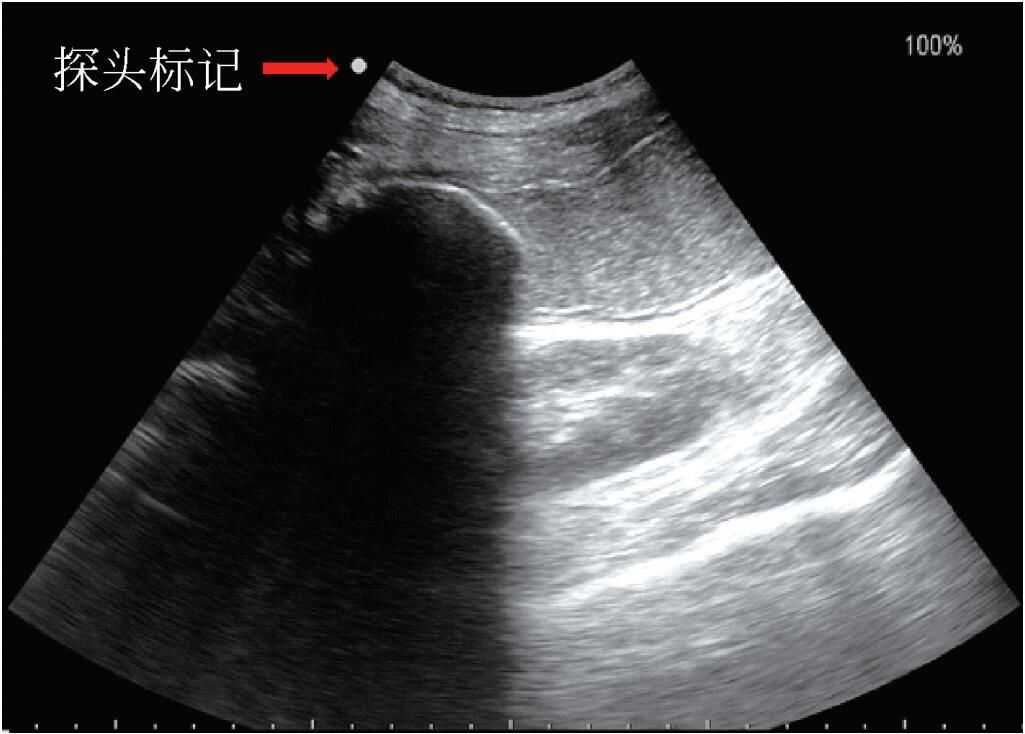

1.探头标记探头的一侧都有一凸起或凹陷的缺口。此标记与屏幕图像上方标记是对应的,以图形、商标或其他标记显示出来,在探头上靠近探头标记的物体就会显示于屏幕上靠近标记的一侧;远离标记的物体就会出现在屏幕标记的对侧。一般情况下,除心脏超声的标记在屏幕的右侧外,其他超声显示的标记均在屏幕左侧。一般手持探头时,右手示指指向探头标记,探头标记指向患者的头则或右侧(图4)。

图4标记方位